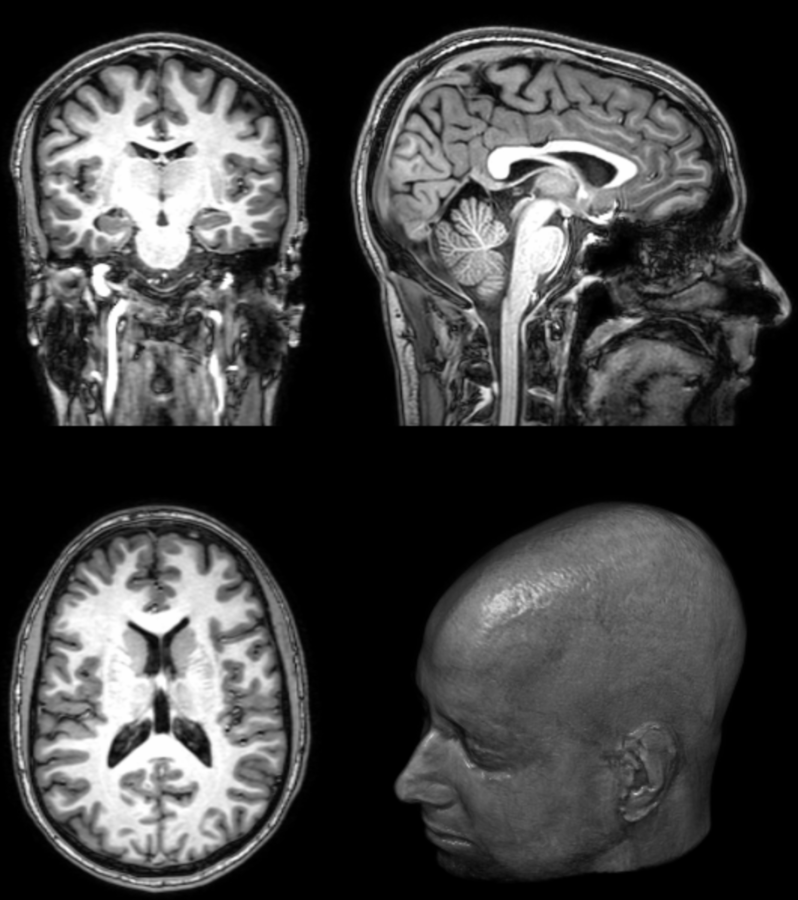

2. State of the art

1. Registration (rigid, affine, nonlinear)

2. Correction (Bias Field, Lesion Filling,

Motion Correction, PVC)

3. Segmentation (Manual, Template-based)

4. Measurement (mean, std over VOIs)

Registration

Correction

Motion Correction

Partial Volume Correction

Segmentation

Measurements

Cortical Thickness Estimation

Pipelining